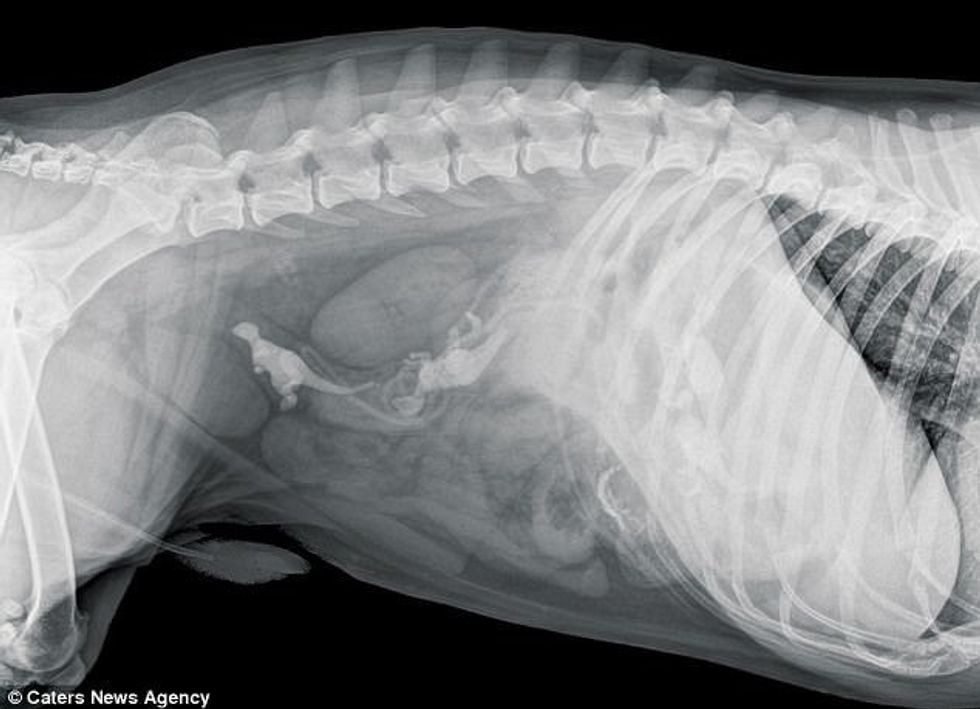

Këtë vit ishte fitues një bulldog, që kishte përpirë një bri dhe një lodër që ngjanë me ashtin, transmeton Telegrafi.